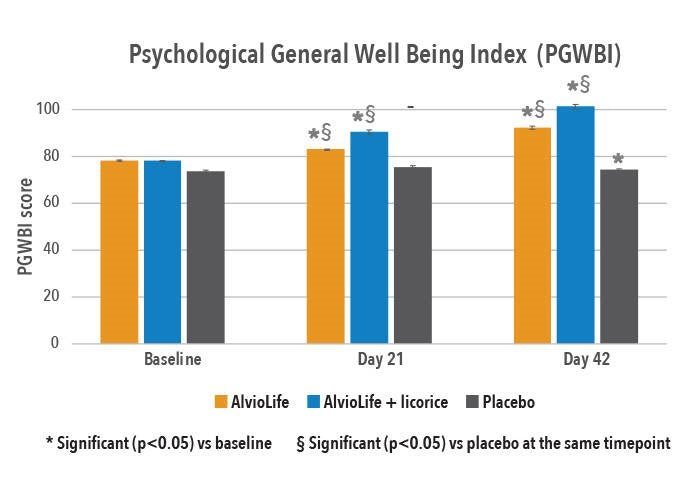

Etude clinique sur AlvioLife® pour le confort respiratoire – Revue internationale des sciences médicales (2021)